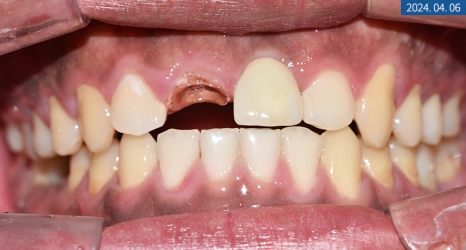

상담을 할 때 환자분께서

부드러운 음식만 주로 먹게 될 만큼

앞니가 많이 불편해요.

라고 하셨는데요.

X-ray 상 앞니 손상과 치근 염증이

심하다는 결과를 봐서는 발치가 필요해 보였으며

좌측 하악 어금니도 뿌리 밑에 염증이 생겨

치아 보존이 힘든 상황이었습니다.

그만큼 치아 강직과 만성 복합치주염으로 인한

난발치 상황이었죠.

우측도 파열돼있었지만

우선 치주 치료를 하면서 지켜봐도

좋을 것 같다는 판단이 들었습니다.